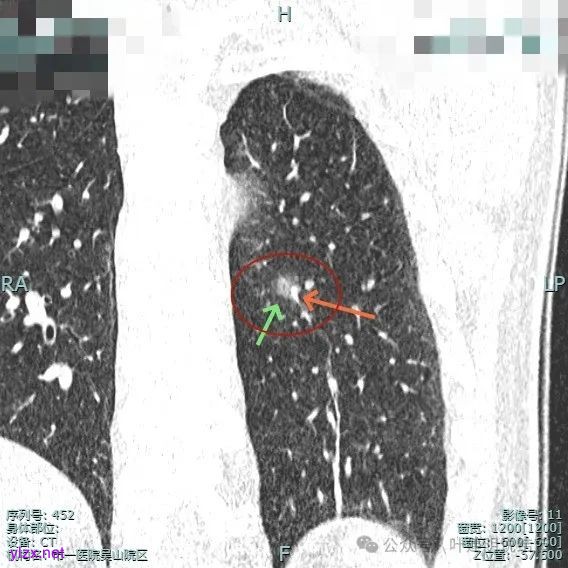

主病灶实性成分明显,表面有毛刺,边缘不平毛糙;次病灶密度纯且淡,轮廓清楚。

主病灶有血管进展与异常增粗,灶内有实性成分,中间有小空泡征。

轮廓清,血管明显。

灶内小空泡征,边缘略显毛糙,整体轮廓较清。

血管进入扭曲,毛刺明显,整体轮廓清,灶内小空泡征。

主病灶血管进入,灶内空泡,表面浅分叶,整体轮廓较清。